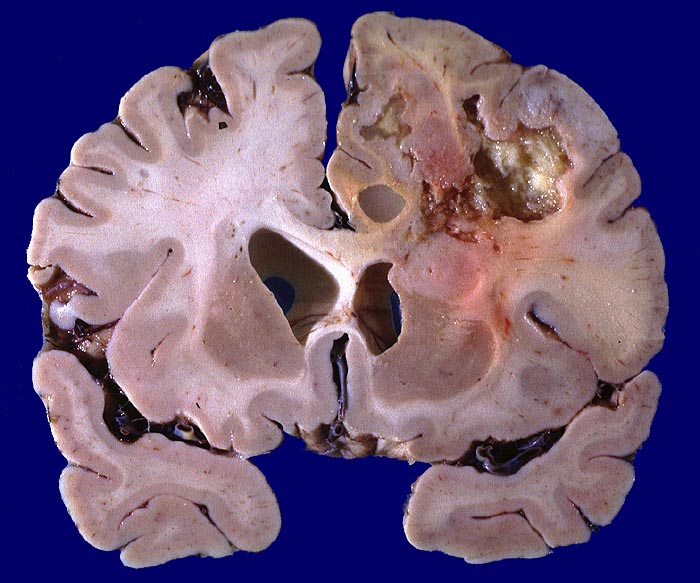

Morphologie:

Die Schnittfläche ist auffallend bunt. Dies ist bedingt durch ein Nebeneinander von graurotem vitalem Tumorgewebe, gelben Nekrosen, roten Einblutungen und gelegentlich grünlichen Gallertzysten.